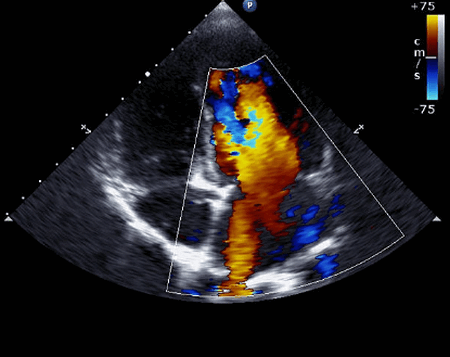

ЭхоКГ после миэктомии и миотомии по поводу гипертрофической кардиомиопатии (ГКМП)

Обструктивная ГКМП характеризуется гипертрофией миокарда ЛЖ при отсутствии дилатации полости желудочка, а также наличием обструкции его выходного тракта. Это приводит к возникновению и прогрессированию хронической сердечной недостаточности и повышает риск внезапной сердечной смерти. Основными причинами обструкции выходного отдела ЛЖ при ГКМП являются SAM-синдром и гипертрофия МЖП, а также аномальное расположение хорд и папиллярных мышц [27—33]. ЭхоКГ является одним из важнейших методов диагностики данной патологии и позволяет визуализировать причину обструкции выходного отдела ЛЖ, степень гипертрофии ЛЖ, а также с помощью допплеровского анализа оценить внутрижелудочковый и аорто-желудочковый градиенты давления [34—36]. Последний используют в качестве основного диагностического критерия для определения стратегии лечения заболевания. B. Maron [34] выделил 3 формы ГКМП:

С помощью допплеровского анализа можно получить достоверные данные о существующем градиенте давления между ЛЖ и аортой по пиковой скорости кровотока в выходном тракте ЛЖ [26, 41]. Однако стоит иметь в виду, что митральная регургитация может искажать данные о градиенте давления и приводить к гипердиагностике [42, 43].